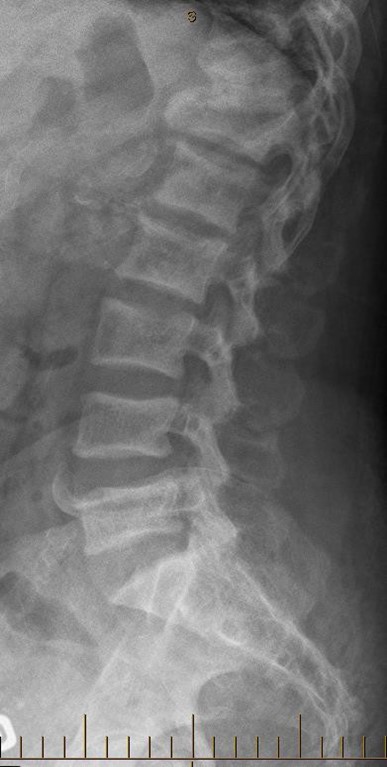

Given the persistent bone pain coupled with a very high TALP, it was decided to complete the workup to further characterise her bone disorder. An alkaline phosphatase electrophoresis was performed, which confirmed that 97% of the TALP was of bone origin. Plain radiographs were also performed. Radiographs of her knees and hands were suggestive of hyperparathyroidism, with subperiostal resorption (Figure 2). The skull radiograph demonstrated a salt and pepper skull (Figure 2). Finally, radiographs of her spine showed a rugger jersey spine (Figure 4), a brown tumor at D12, as well as multiple vascular calcifications. Magnetic resonance imaging of her spine confirmed the presence of and better characterised the brown tumor (Figure 5). A bone scan ruled out Paget’s disease. It is to be noted that she did not undergo a bone biopsy due to lack of accessibility.

Figure 4: Radiograph of the patient’s spine, showing a rugger jersey spine